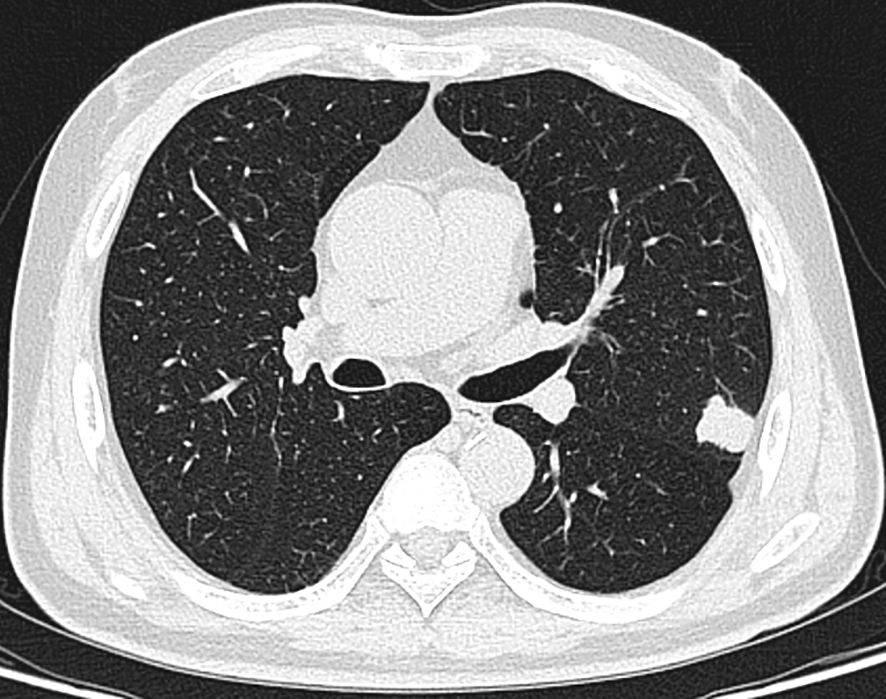

A 66-year-old male patient was admitted to our hospital’s thoracic surgery department on November 5, 2024. Due to a “left lung upper lobe nodule discovered during a routine physical examination for over one month.” The patient had a chest CT scan at a physical examination center one month ago, which revealed a nodule in the posterior segment of left upper lobe. A follow-up enhanced chest CT at our hospital showed multiple nodules in both lungs, with left upper lobe being the most prominent, measuring approximately 1.2 cm × 0.6 cm, and the margin appearing lobulated. Other small nodules with a diameter of less than 0.5 cm, recommended for follow-up observation (Figure 1). The patient reported having a morning cough with white, sticky sputum. He has a history of cerebral infarction for 8 years and hypertension for over 10 years. The patient also has a long history of heavy smoking and drinking for over 40 years. Physical examination upon admission showed no significant abnormalities. Liver and kidney function tests indicated: total protein 59.1 g/L, albumin 36.5 g/L, with no other abnormalities. Routine blood, urine, stool, thyroid function, coagulation, Arterial blood gas analysis and cardiac enzyme tests were normal. Pulmonary function tests showed forced expiratory volume in one second/forced vital capacity (FEV1/FVC) of 69.5%, FEV1 of 1.76 L (63.4% of predicted value), total lung capacity (TLC) at 99.5% of predicted value, and diffusing capacity of the lungs for carbon monoxide (DLCO) at 93.4% of predicted value, indicating moderate obstructive ventilatory dysfunction. Electrocardiogram showed: 1. sinus rhythm, 2. abnormal Q waves (II, III, aVF), 3. incomplete right bundle branch block. Coronary CTA showed severe stenosis in the mid-segment of left anterior descending artery and diagonal branch, with the remaining coronary arteries showing mild stenosis. Brain MRI showed mild brain atrophy. Ultrasound examinations of the heart, liver, gallbladder, pancreas, spleen, kidneys, neck arteries, and lower extremity veins, along with whole-body bone scintigraphy, showed no significant abnormalities. After excluding contraindications for surgery, the patient underwent thoracoscopic left upper lobectomy under general anesthesia on November 11. Due to the diameter of other small lung nodules being less than 0.5 cm, regular follow-up observation is recommended and no intervention was performed during the surgery. Intraoperative dissection of lymph nodes from groups 5, 7, 10 and 11. Intraoperative frozen section pathology indicates invasive carcinoma and subsequent routine paraffin-embedded pathology (Figure 2) showed immunohistochemistry results: CK5/6 (partially +), P40 (partially +), P63 (partially +), CK7 (focally +), Napsin A (-), TTF-1 (+), Ki67 (+, approximately 70%), CD56 (+), CgA (-), Syn (+). Based on immunohistochemistry, the diagnosis was composite small cell carcinoma (95% small cell carcinoma + 5% squamous cell carcinoma). The tumor measured approximately 1.4 × 1 × 0.7 cm and had not invaded pleura. No metastatic cancer was found in lymph nodes. According to pathological report, the staging was T1bN0M0 IA2. After surgery, the patient received one cycle of chemotherapy and immunotherapy with the following regimen: albumin-bound paclitaxel 300 mg, carboplatin 700 mg, and serplulimab 300 mg. After discharge, the patient reported no significant discomfort. Chest CT re-examination at 1st and 3rd month post-surgery showed no significant abnormalities (Table 1).

Figure 1

CT scan of a chest showing a transverse section of the lungs. The image reveals the airways, lung tissue, and various densities indicating possible abnormalities or variations. The heart and major vessels are also partially visible.

Figure 1. A nodule in the left upper lobe, with the edges appearing lobulated.